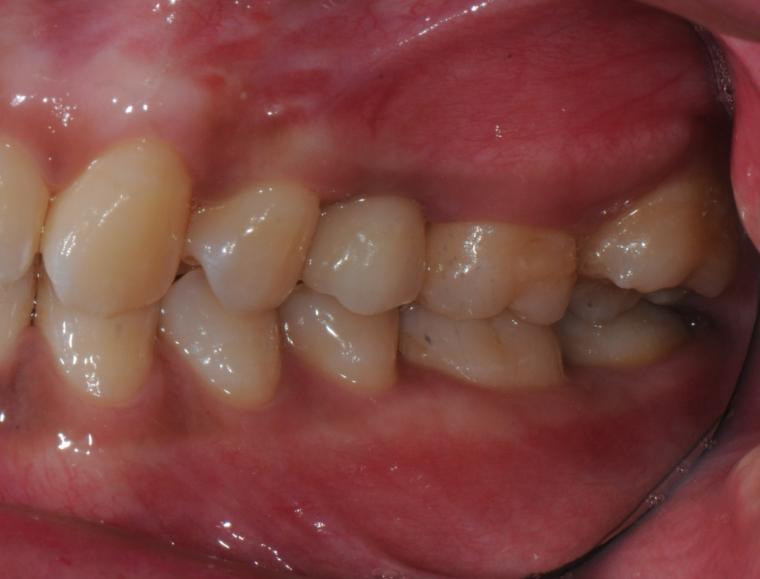

AFTER

33歳女性/上顎1本欠損/インプラント埋込手術

欠損部にインプラントが入り、現在は定期健診で拝見させていただいています。